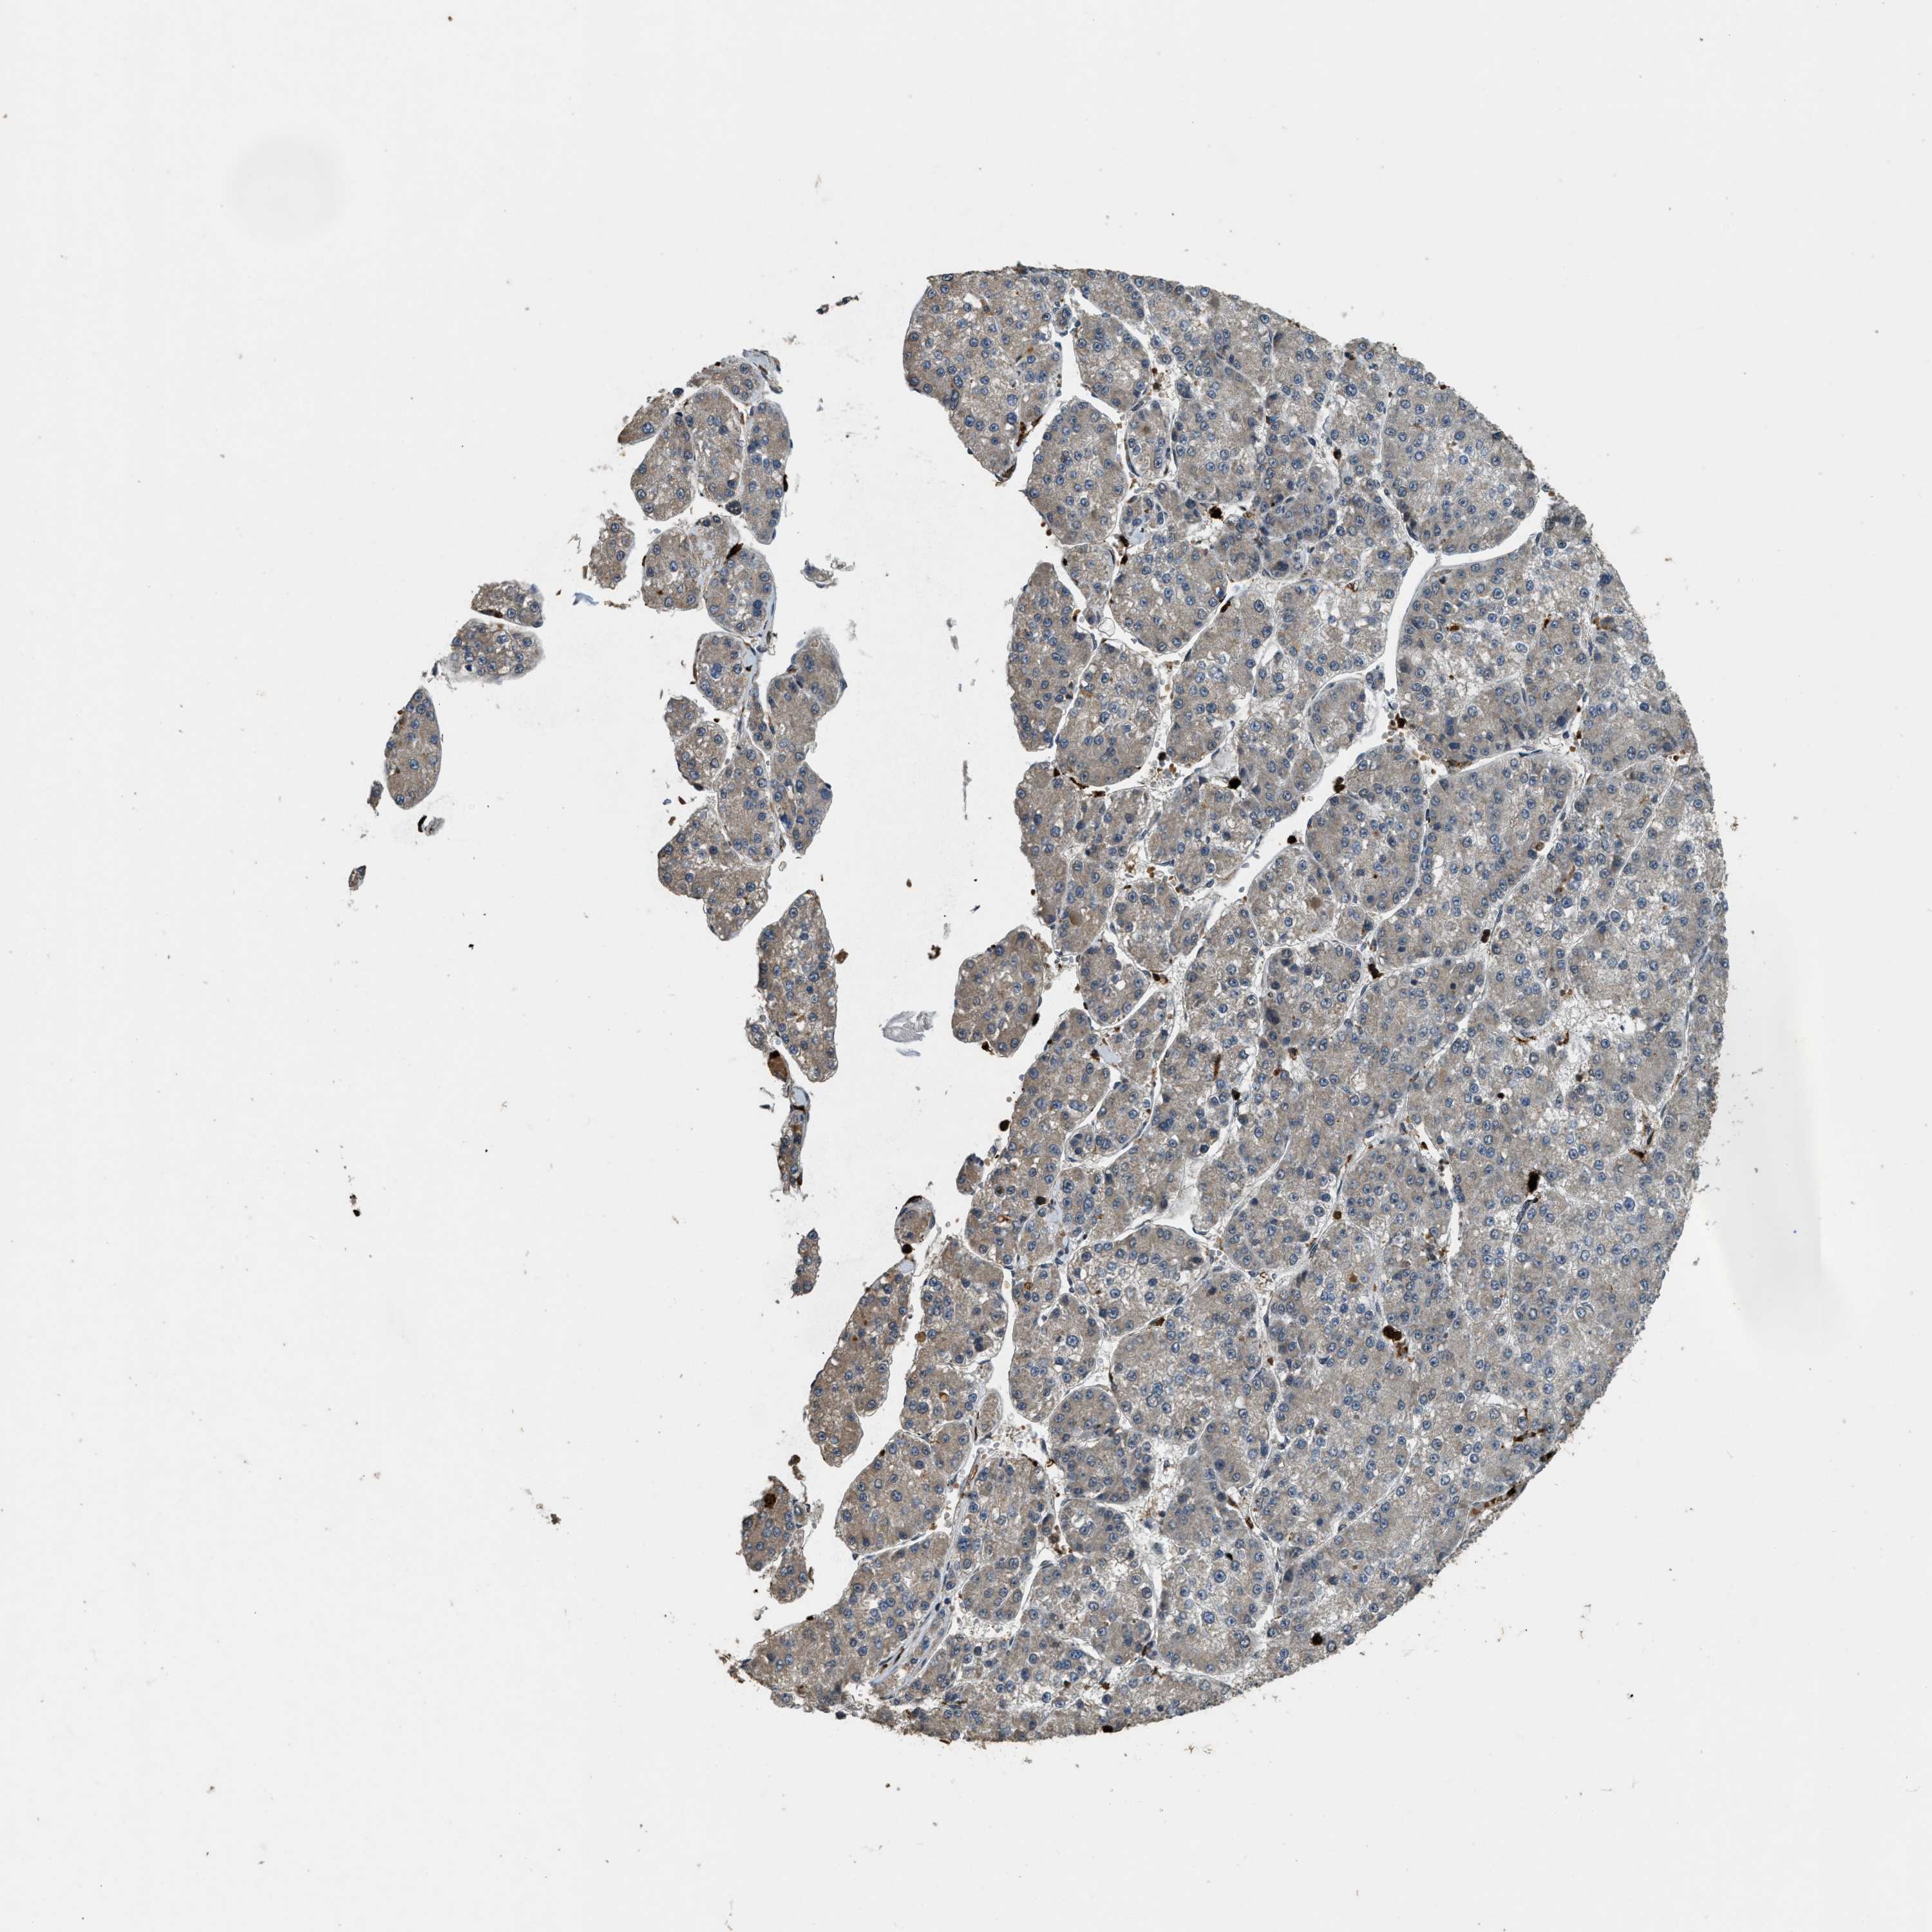

LIVER CANCER - Protein expressioni

A mouse-over function shows sample information and annotation data. Click on an image to view it in a full screen mode. Samples can be filtered based on level of antibody staining by selecting one or several of the following categories: high, medium, low and not detected. The assay and annotation is described here.

Note that samples used for immunohistochemistry by the Human Protein Atlas do not correspond to samples in the TCGA dataset.

Antibody stainingi

Antibody staining in the annotated cell types in the current human tissue is reported as not detected, low, medium, or high, based on conventional immunohistochemistry profiling in selected tissues. This score is based on the combination of the staining intensity and fraction of stained cells.

Each image is clickable and will lead to virtual microscopy that enables deeper exploration of all samples and also displays staining intensity scores, fraction scores and subcellular localization as well as patient and tissue information for each sample.

Antibody HPA018133

Staining

High

Medium

Low

Not detected

Intensity

Strong

Moderate

Weak

Negative

Quantity

>75%

75%-25%

<25%

None

Location

Nuclear

Cytoplasmic/membranous

Cytoplasmic/membranous,nuclear

Cholangiocarcinoma

Carcinoma, Hepatocellular, NOS